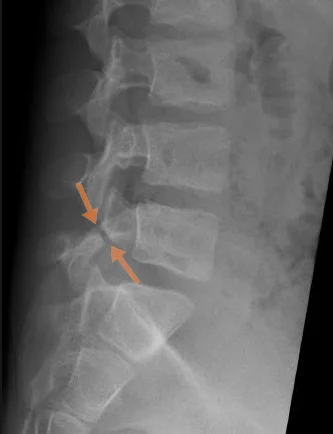

- X-ray (lumbosacral radiograph) is usually the first imaging method and can reveal a pars interarticularis defect, especially if a complete fracture is present. However, X-rays are not sensitive enough for early cases or stress fractures, where the fracture line may not yet be clearly visible.

- CT scan (computed tomography) provides a more detailed view of bony structures and is considered the gold standard for visualizing pars interarticularis fractures. CT also has limitations: it is less suitable for early stress fractures that have not yet formed a complete crack, and radiation exposure is much higher than with standard X-rays, which is important to consider, especially in children.